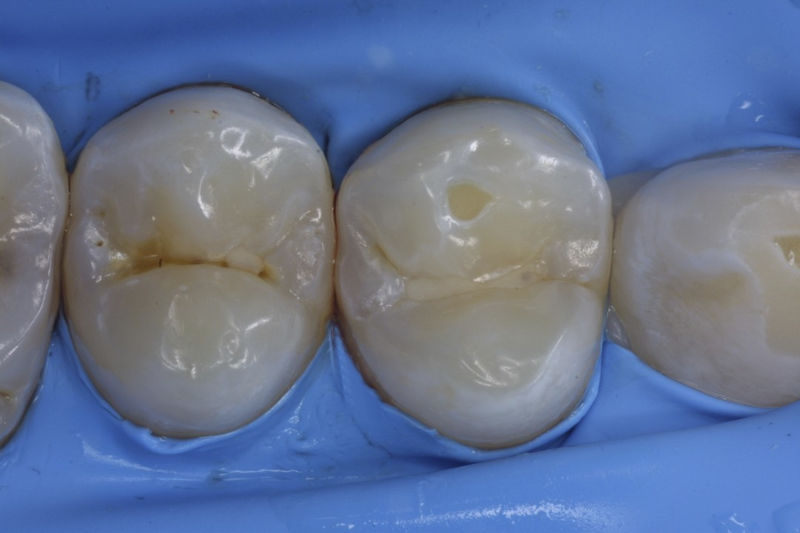

Restauraciones fabricadas en el laboratorio con materiales estéticos, los cuales cubren de manera parcial dientes posteriores. Se utilizan primariamente para restaurar dientes con caries, fracturas y/o defectos amplios. Para poder enviar el caso al laboratorio se toman impresiones utilizando materiales de impresión o técnicas modernas digitales.